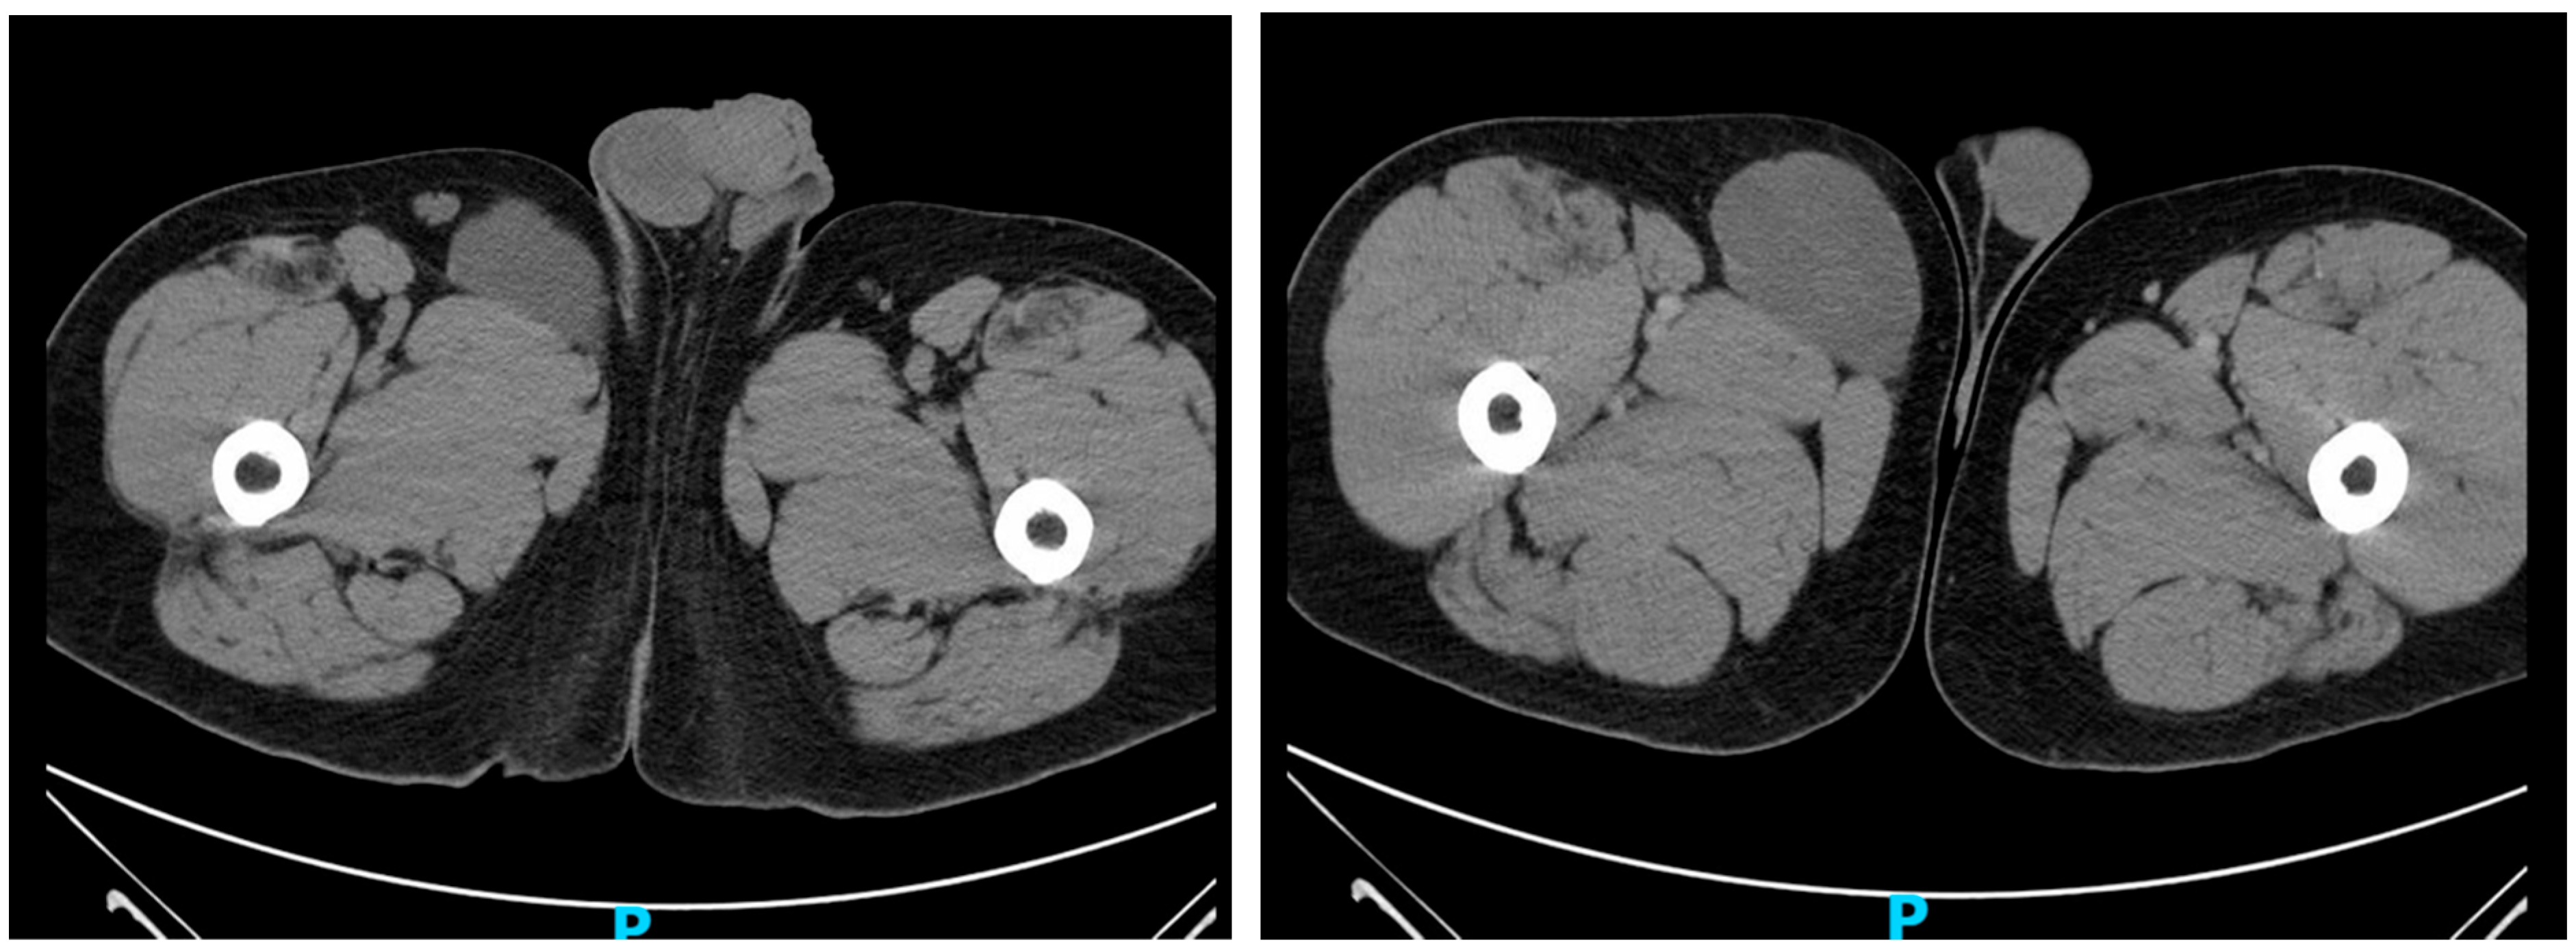

A contrast-enhanced CT scan of the abdomen and pelvis revealed an incompletely imaged, circumscribed, low-attenuation lesion within the medial aspect of the right thigh subcutaneous soft tissue measuring 7.3 × 5.6 cm (Figure 1). This was of uncertain etiology and could reflect a complex cystic lesion, thus ultrasound correlation was advised. An ultrasound of the region further characterized the lesion as a complex hypoechoic, likely solid mass, with dimensions of 10.5 cm × 4.5 cm × 9.4 cm (Figure 2). The differential diagnosis at this point included a neoplasm, though a benign process could not be excluded.

Figure 1. CT Abdomen and Pelvis incompletely imaged the circumscribed low-attenuation lesion within the medial aspect of the right thigh subcutaneous soft tissues measuring 7.3 × 5.6 cm. This lesion demonstrates CT Hospital units averaging 19 which cannot be characterized as a simple cystic fluid with certainty.